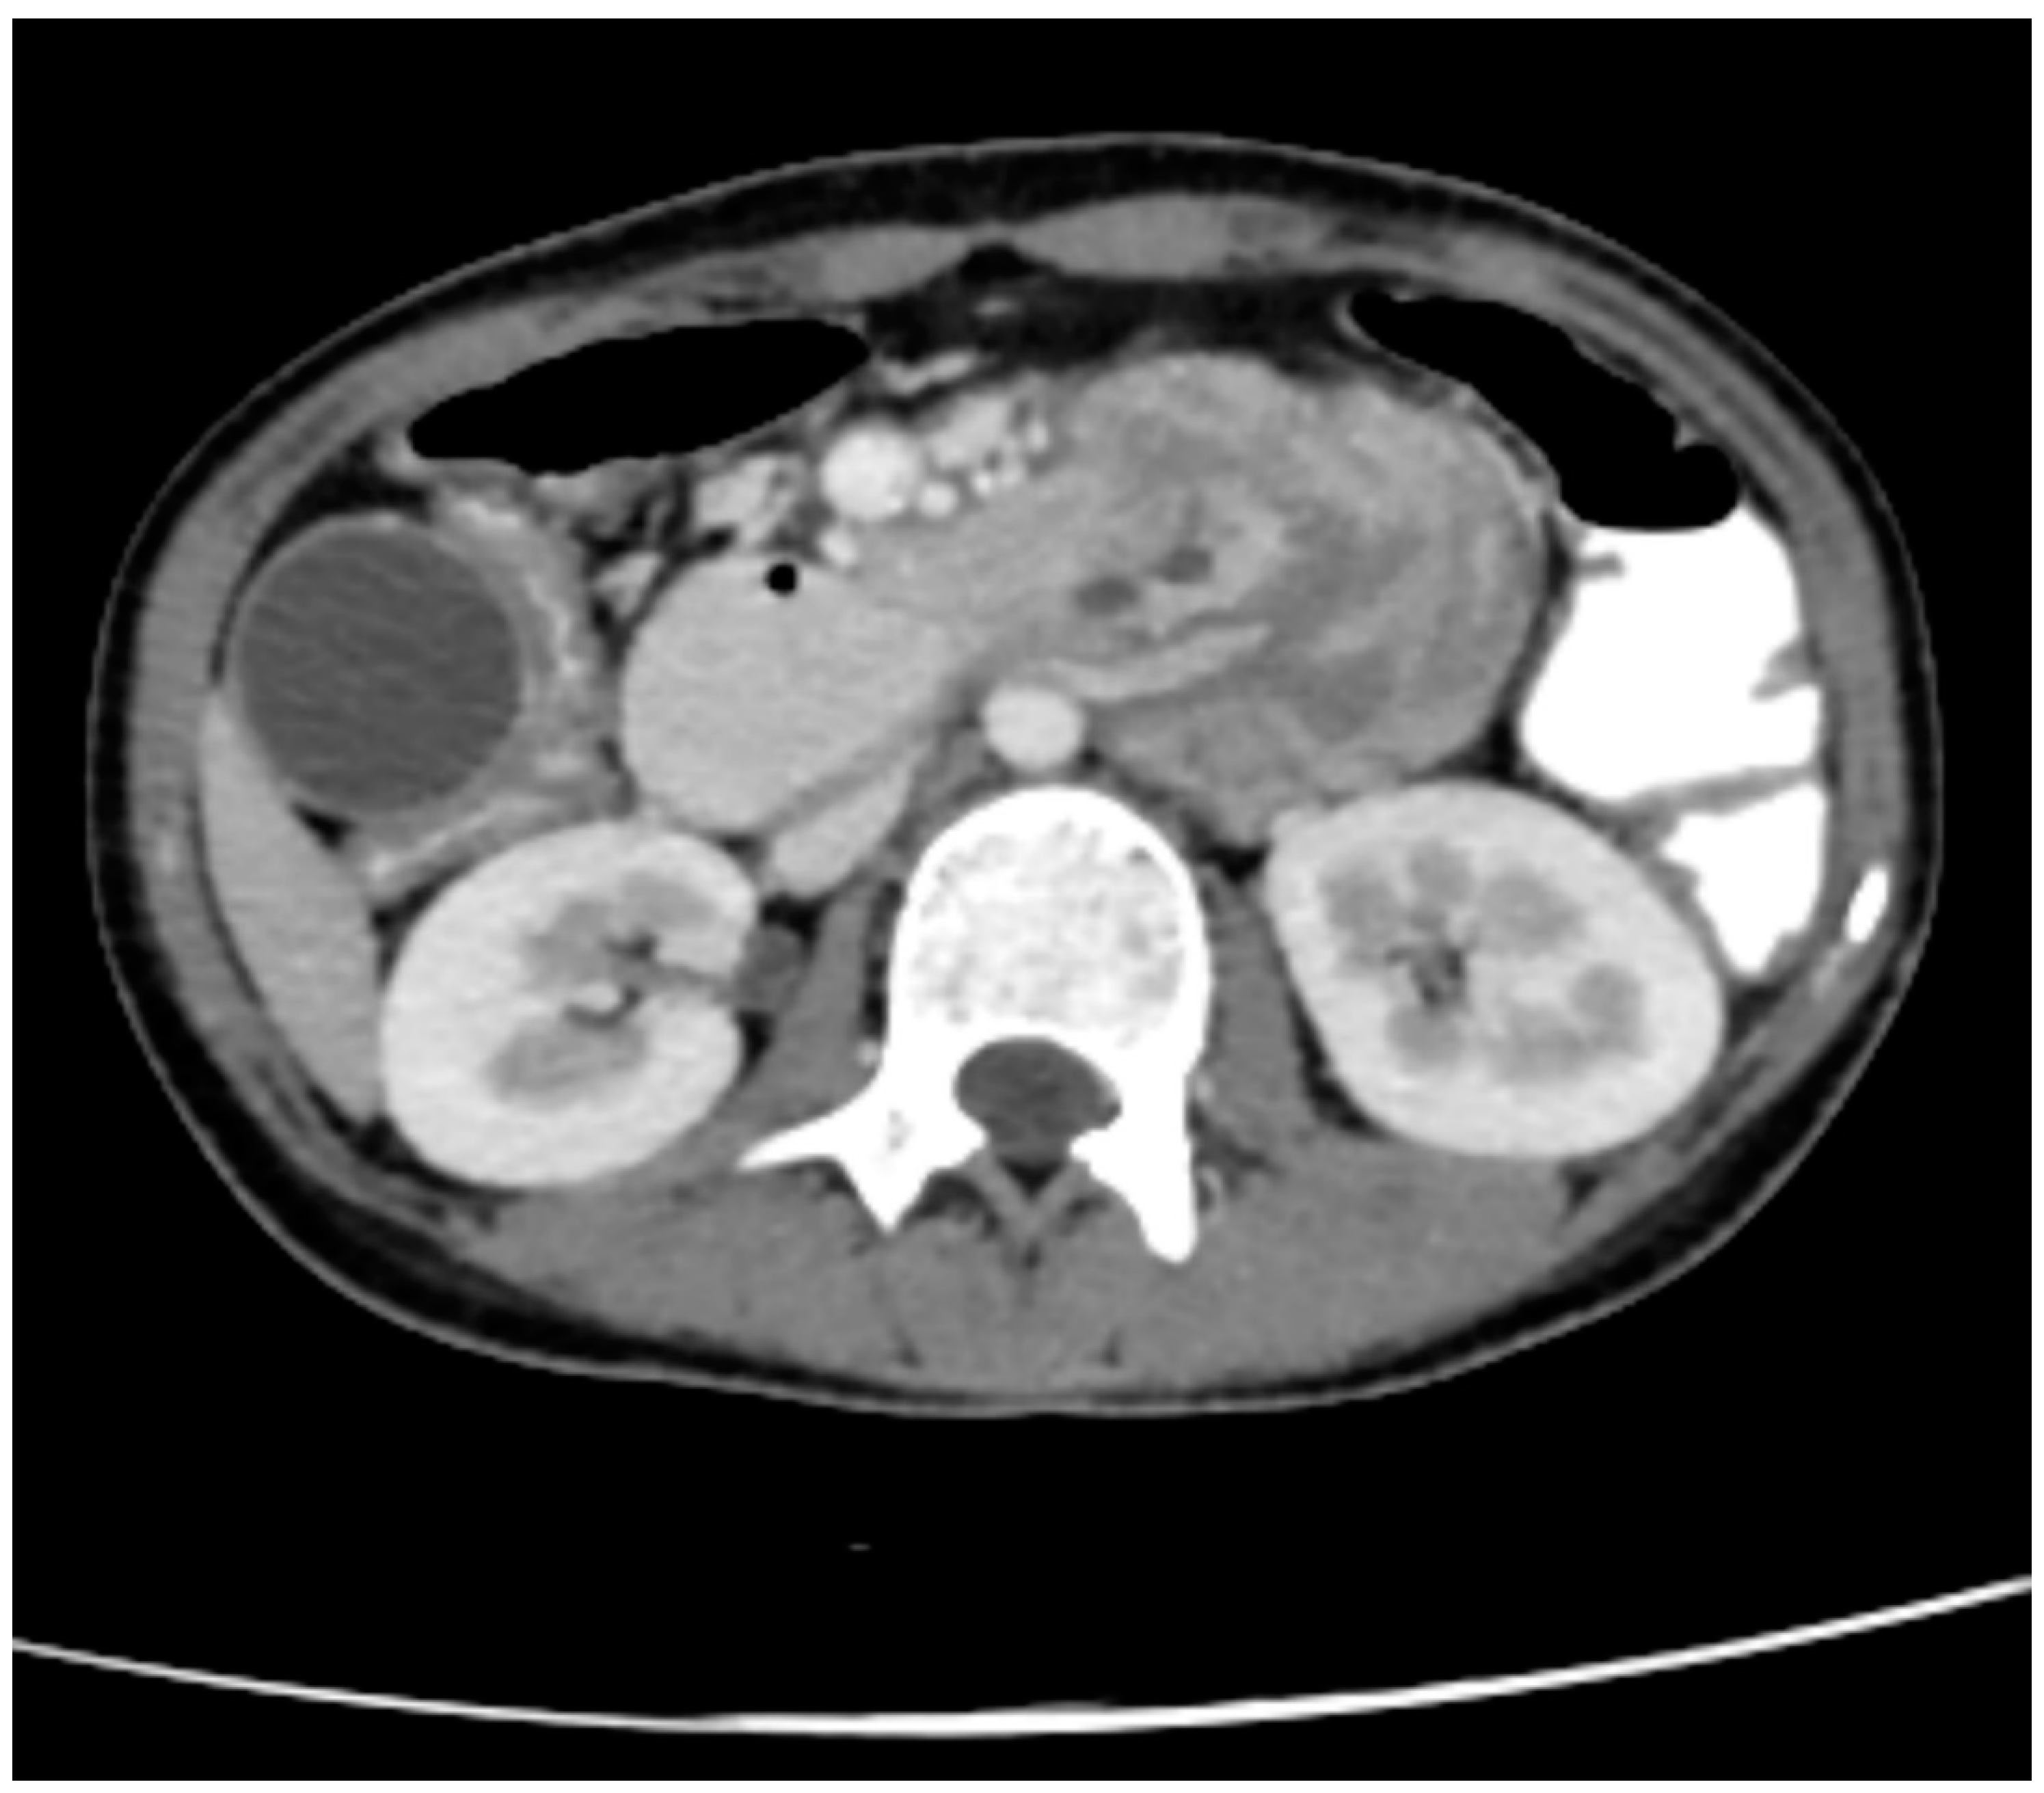

Figure 2. CECT Axial Abdomen showing Head of the pancreas, 2nd part of the duodenum, and ampulla of Vater entering into 3rd part of the duodenum.

The Intussusceptum is 2nd part of the duodenum, the ampulla of the Vater, the head, and the uncinate process of the pancreas while the intussusipens is 3rd and 4th part of the duodenum. The content of the Intussusceptum shows homogenous post-contrast enhancement. The length of the Intussusceptum measures approximately 7 cm.

The Intussuscipens shows enhancing reactionary wall thickening of the 3rd and 4th part of the duodenum and proximal jejunum, maximum wall thickness measures approximately 8 mm of the 4th part of the duodenum. The Intussusceptum does not show any obvious mass lesion or lead point, however underlying ampullary lesion cannot be ruled out owing to the presence of a double duct sign.